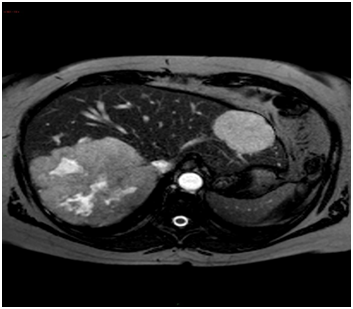

A 55-year old woman presented at the outpatients clinic with right upper quadrant pain and abdominal distention. A year before she was diagnosed with endometrial carcinoma, stage IA, and underwent abdominal hysterectomy and removal of both ovaries. She had not received oral contraceptives in the past. Pre-operative evaluation for extent of disease had shown several lesions in the liver suspicious of hemangiomas on ultrasonography. The two largest lesions were 19 and 5cm respectively. Computed tomography and magnetic resonance imaging supported the diagnosis. The giant hemangioma was located in an enlarged right lobe of the liver and the smaller one in the left lobe (Figure 1).

Figure 1 MRI with two haemangiomas in the right and left liver lobe.